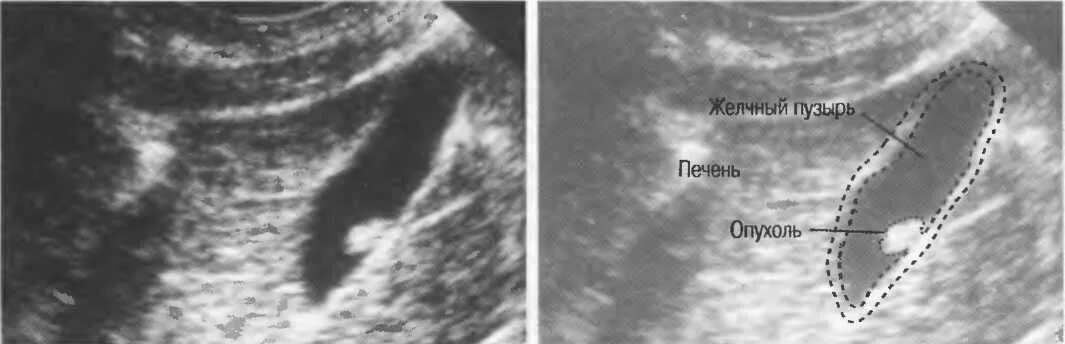

Стенка желчного уплотнена что это